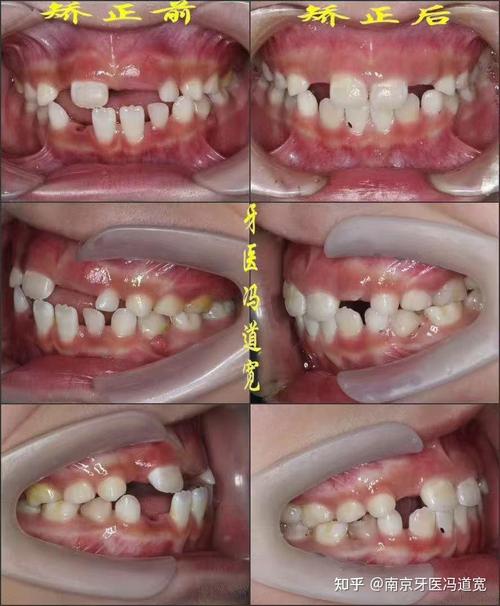

反颌,俗称“地包天”,是一种常见的错颌畸形,表现为上前牙咬合时位于下前牙舌侧,或上下前牙交叉咬合,不仅影响咀嚼功能和面部美观,还可能对心理健康造成困扰,正畸治疗是矫正反颌的主要手段,其过程需通过系统化的方案设计和精细化的操作,逐步引导牙齿、颌骨恢复到正常位置。

这是反颌治疗的核心,通过施加持续、轻柔的力,引导牙齿、牙槽骨改建,逐步纠正反颌关系,根据矫正器类型,可分为传统托槽矫正和隐形矫正,具体操作如下:

牙齿移动的阶段性目标

- 排齐整平期(1-6个月):解决牙齿拥挤、扭转,将弓丝纳入托槽槽沟,利用镍钛丝的弹性将牙齿排齐,整平Spee曲线。

- 关闭拔牙间隙/调整咬合期(6-18个月):通过滑动法或关闭曲法内收前牙,纠正反颌关系,同时调整磨牙咬合,建立中性咬合(上颌第一磨牙近中颊尖咬在下颌第一磨牙颊沟)。